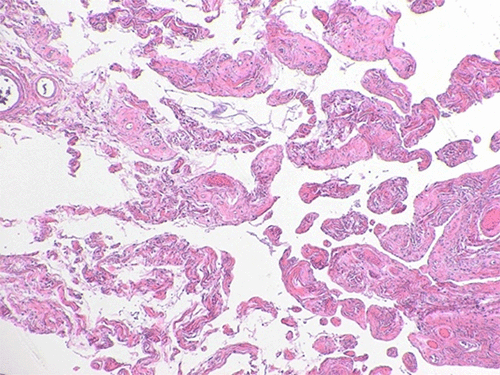

The final pathology report was consistent with a pseudoangiomatous spindle cell lipoma. Grossly, the soft tissue mass was red to yellow in color, well-circumscribed, and measured 19.0 × 9.6 × 3.3 cm. Upon palpation, the mass appears gelatinous with central firm nodular areas. Serial sectioning revealed a pink-tan heterogenous and multilobulated cut surface with areas of myxoid change and cystic degeneration. Focal areas of hemorrhage were also noted. The impression of firm pink to tan nodules centrally was confirmed (Figure 3).

Figure 3. Surgical Pathology. Published With Permission

A) 2x: Tumor contained broad collagenous areas with interspersed benign lipomatous elements

B) 4x: Tumor also demonstrated islands of collagenous and vascular stroma surrounded by pseudovascular channels

C) 10x: Ropey collagen was present diffusely throughout tumor, distinct pathologic finding in spindle cell lipomas

D) 20x: Bland-appearing spindle cells in background of ropey collagen